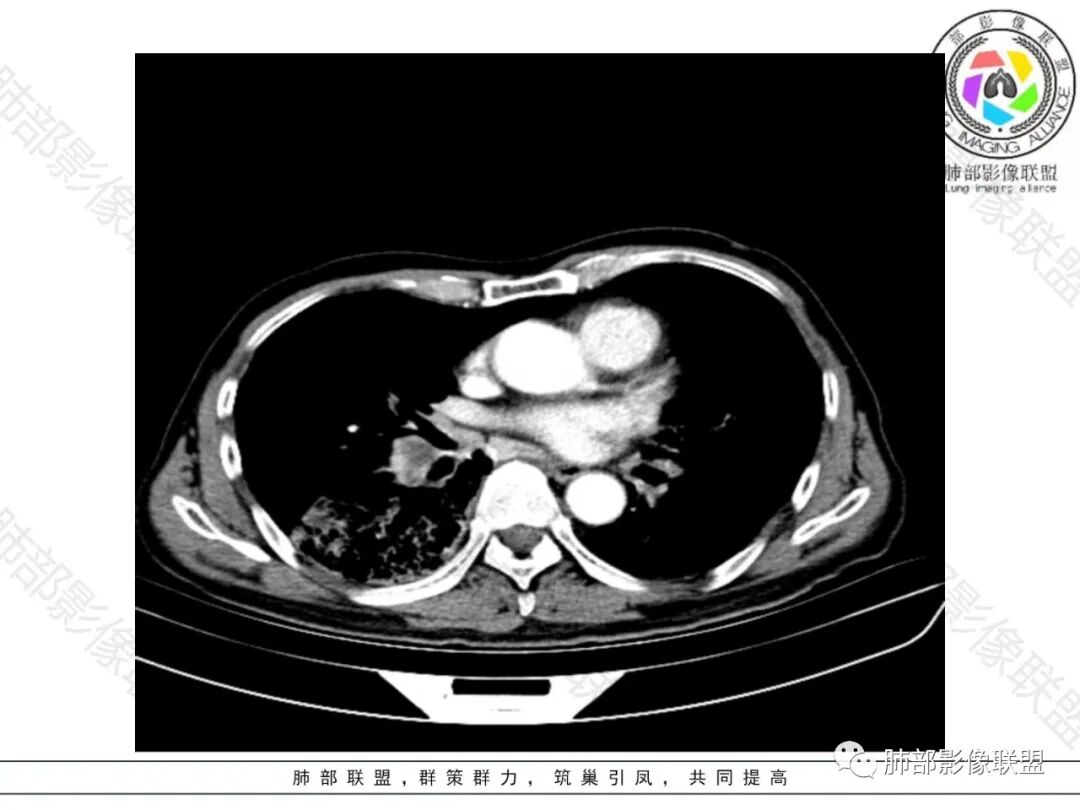

右肺下叶大团块影,斜裂膨隆,内支气管破坏,纵隔窗实质性成份少有强化(假大空),肿瘤CA125、199高,考虑粘液腺Ca右肺门淋巴结及纵隔淋巴结大,右肺下动干起始处充盈缺损(示栓塞或Ca栓;余肺叶弥散网格状改变,间质增厚及纤维化表现!

老年男性的病人。慢性的咳嗽憋喘为主的症状,慢性的病程。临床ca199明显的增高,癌胚抗原升高。白细胞增高提示有肺部感染的。影像学表现两肺弥漫性的网格状改变。而病变又集中在右肺下叶。右肺门见一个大结节的病灶,内部有片状坏死,不均匀的强化,邻近的支气管变窄,周围的肺组织呈大片状的实变影。纵隔淋巴结多个肿大。这样的影像学考虑右侧肺门旁的恶性病变。鳞癌或者粘液性腺癌,伴纵隔淋巴结转移,右肺下叶的癌性淋巴管炎,两肺慢性的间质性肺炎。

老年男性,反复咳嗽咳痰喘憋8年,加重10天,发热半天。白细胞计数明显升高(存在细菌感染可能),CEA、CA19—9升高(肺癌或间质性肺疾病引起可能)。痰培养见肺克。CT;双肺弥漫小叶间质、中轴间质增厚,胸膜下肺气肿,右肺门及右下叶可见实变影,边界模糊,内支气管走形僵硬,部分见蜂窝样改变,增强后实变区可见低密度区(粘液?),叶间裂膨隆,纵隔及右肺门见肿大淋巴结,右肺门淋巴结内见坏死。存在感染,但单纯感染难以解释支气管走行僵硬、实变内的低密度病灶,考虑恶性伴感染,肺炎性肺癌或黏液腺癌。

整个背景是一个肺气肿并间质纤维化,肺气肿以上肺为主(有些地方分不清到底是小叶中心或间隔下肺气肿伴间隔增厚还是蜂窝),左肺下叶正常结构消失,以弥漫网格为主,应该没有多少正常肺功能组织。右肺下叶肺动脉栓塞,再往下几层应该是肿大淋巴结并坏死。右肺下叶的病变考虑粘液性腺癌, 需与感染鉴别(有没有可能是肺梗死呢?)

右侧肺门淋巴结肿大,中央低密度;纵隔见轻度增大淋巴结。

3.综合分析:临床方面:慢性病程、急性发作,呼吸道症状伴发热,炎性指标升高,提示存在感染可能;CA199升高,但相对特异性不高。影像双肺气肿,右肺下叶蜂窝状改变明显,夹杂实变密度区,支气管相关但未见阻塞,较常见于感染性病变,如G-杆菌感染等。蜂窝影什么时候出现我们不得而知,实变区周边特征掩盖不清。

前后三月余病灶变化不明显,右肺门异常肿大淋巴结让人警惕恶性病变可能性。

显著肺门淋巴结肿大较少出现在粘液腺癌患者,何况如此大范围病灶未见播散结节。